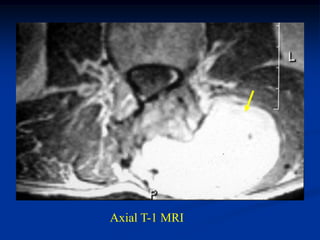

tumor Axial T-1 MRI

Case #1183 Coronal T-1 MRI 51 year male with superficial lipoma arm